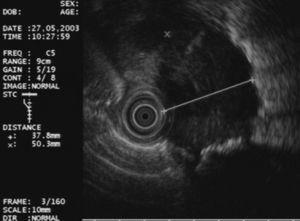

En primer lugar se efectuó una ecoendoscopia diagnóstica usando un ecoendoscopio radial con frecuencias de 5 y 20 MHz (GF UM20 y GF UM160, Olympus America Inc., Melville, NY, EE UU). En todos los casos se realizó una exploración sistemática del mediastino posterior y medio, y de los territorios ganglionares accesibles a la USE (regiones 4R, 4L, 5, 7, 8 y 9) con el fin de identificar y caracterizar morfológicamente las lesiones y establecer la relación entre éstas y las estructuras vecinas (figs. 1 y 2).

Fig. 2. Adenopatía en la región 4L con características ecográficas de malignidad: redonda, hipoecogénica, bien delimitada y diámetro corto de 1 cm.